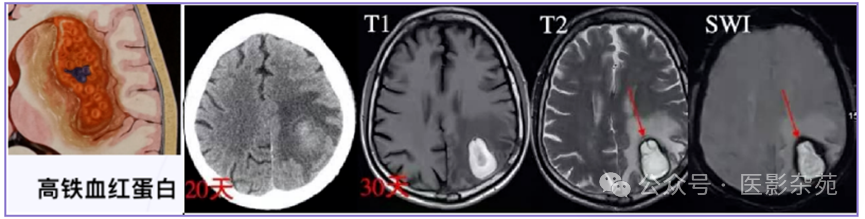

细胞外高铁血红蛋白

T1:保持高信号

T2:在接下来的几周内,随着细胞分解和细胞外高铁血红蛋白的增加,信号逐渐增加

DWI:高

ADC:低